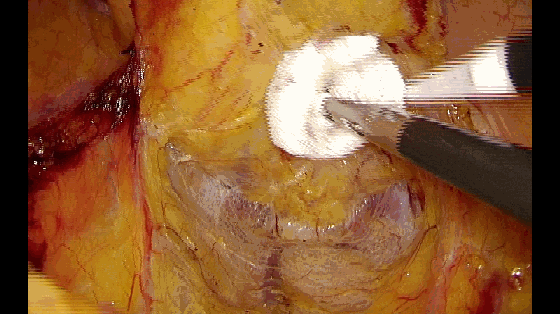

钝性支撑作用

有时用小纱布衬垫后牵拉肠管,可以避免器械直接牵拉造成的误损伤。